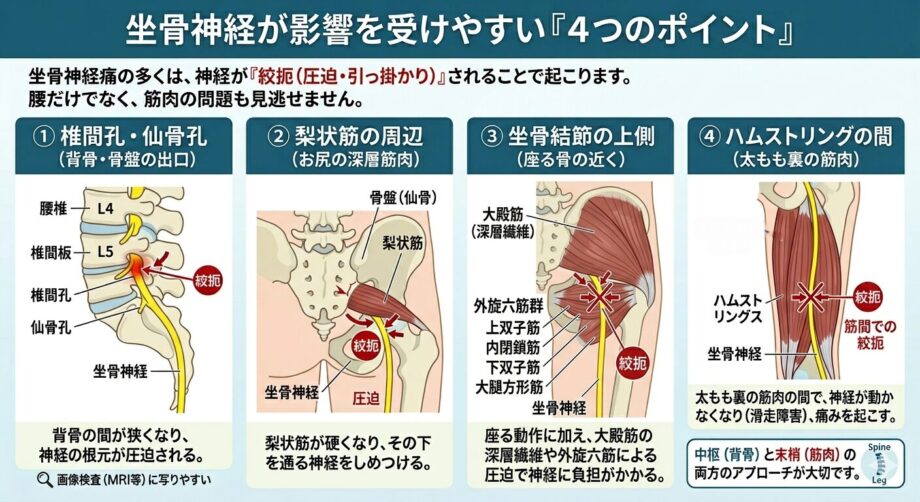

坐骨神経が影響を受けやすい場所

坐骨神経が影響を受けやすい場所

・腰椎や骨盤を出てすぐの所(椎間孔、仙骨孔)

・梨状筋の周辺

・坐骨結節の上側

・ハムストリングの間

などが代表的です。

これらは大きく分けると2つに分けられます。

1つ目の椎間孔や仙骨孔のような中枢に近い所の問題

2つ目は筋肉や皮下組織などの末梢の問題

なんとなく神経痛と言えば、腰が悪いと言うイメージはありませんか?

確かに最初にお話ししたように、神経が骨の間を通過していくところが狭くなり、痛みを引き起こすこともあります。

しかし意外と筋肉や皮下組織などの問題も多く見られるものです。

病院でレントゲンやMRIを撮ったが異常なし。しかし痛みがあるといったケースはほとんどがこれに該当するものと思われます。